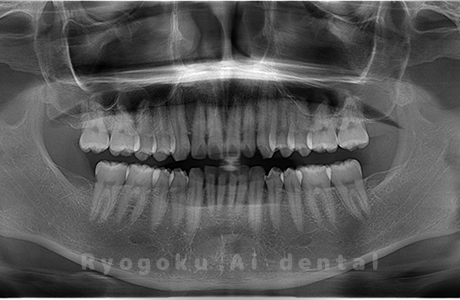

Case01

- 原因

- 水平埋伏智歯

- 治療内容

- 下顎の水平埋伏智歯を抜歯

<リスク・副作用>

手術後は痛み、腫れ、痺れなどの副作用が生じる場合があります。